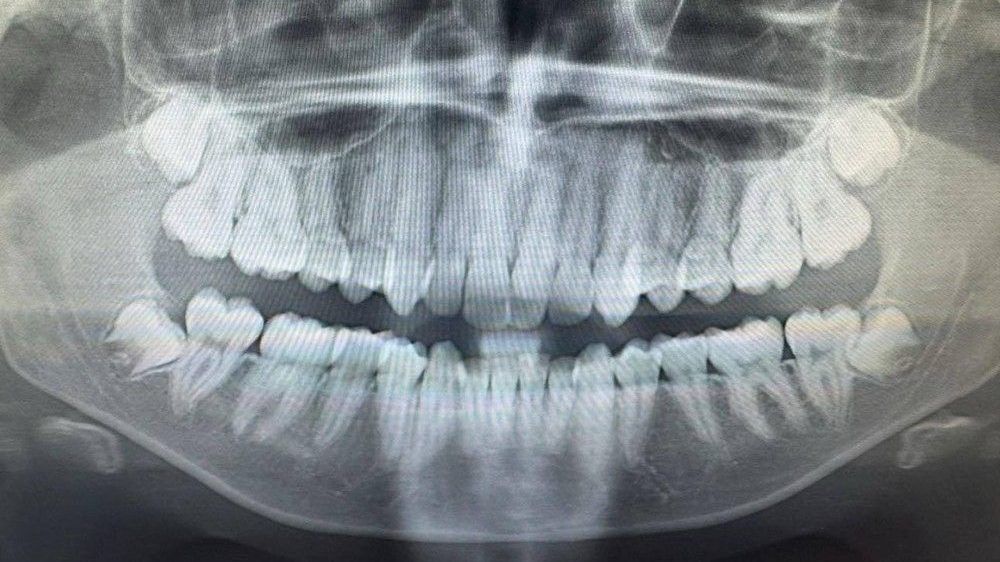

most tooth pain can be managed with a dental procedure, pain relief medication or sometimes a combination of both. antibiotics do not address the cause of most dental pain, which may be caused by cavities, infection or a damaged tooth.